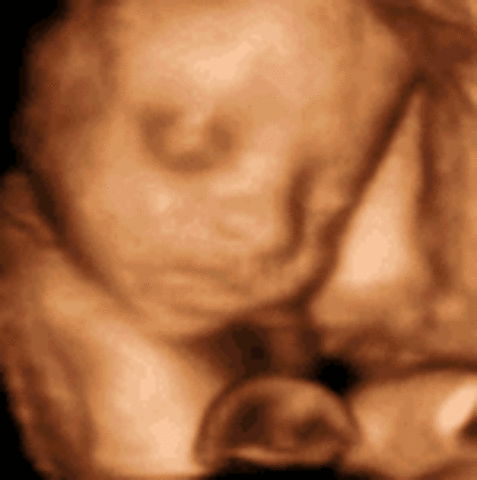

The fetus starts to move. the face begin to look like a baby face.

• Week Thirteen: Baby flexes and kicks

Week Thirteen: Baby flexes and kicks

The movements can be measured. the chin and nose are well defined.